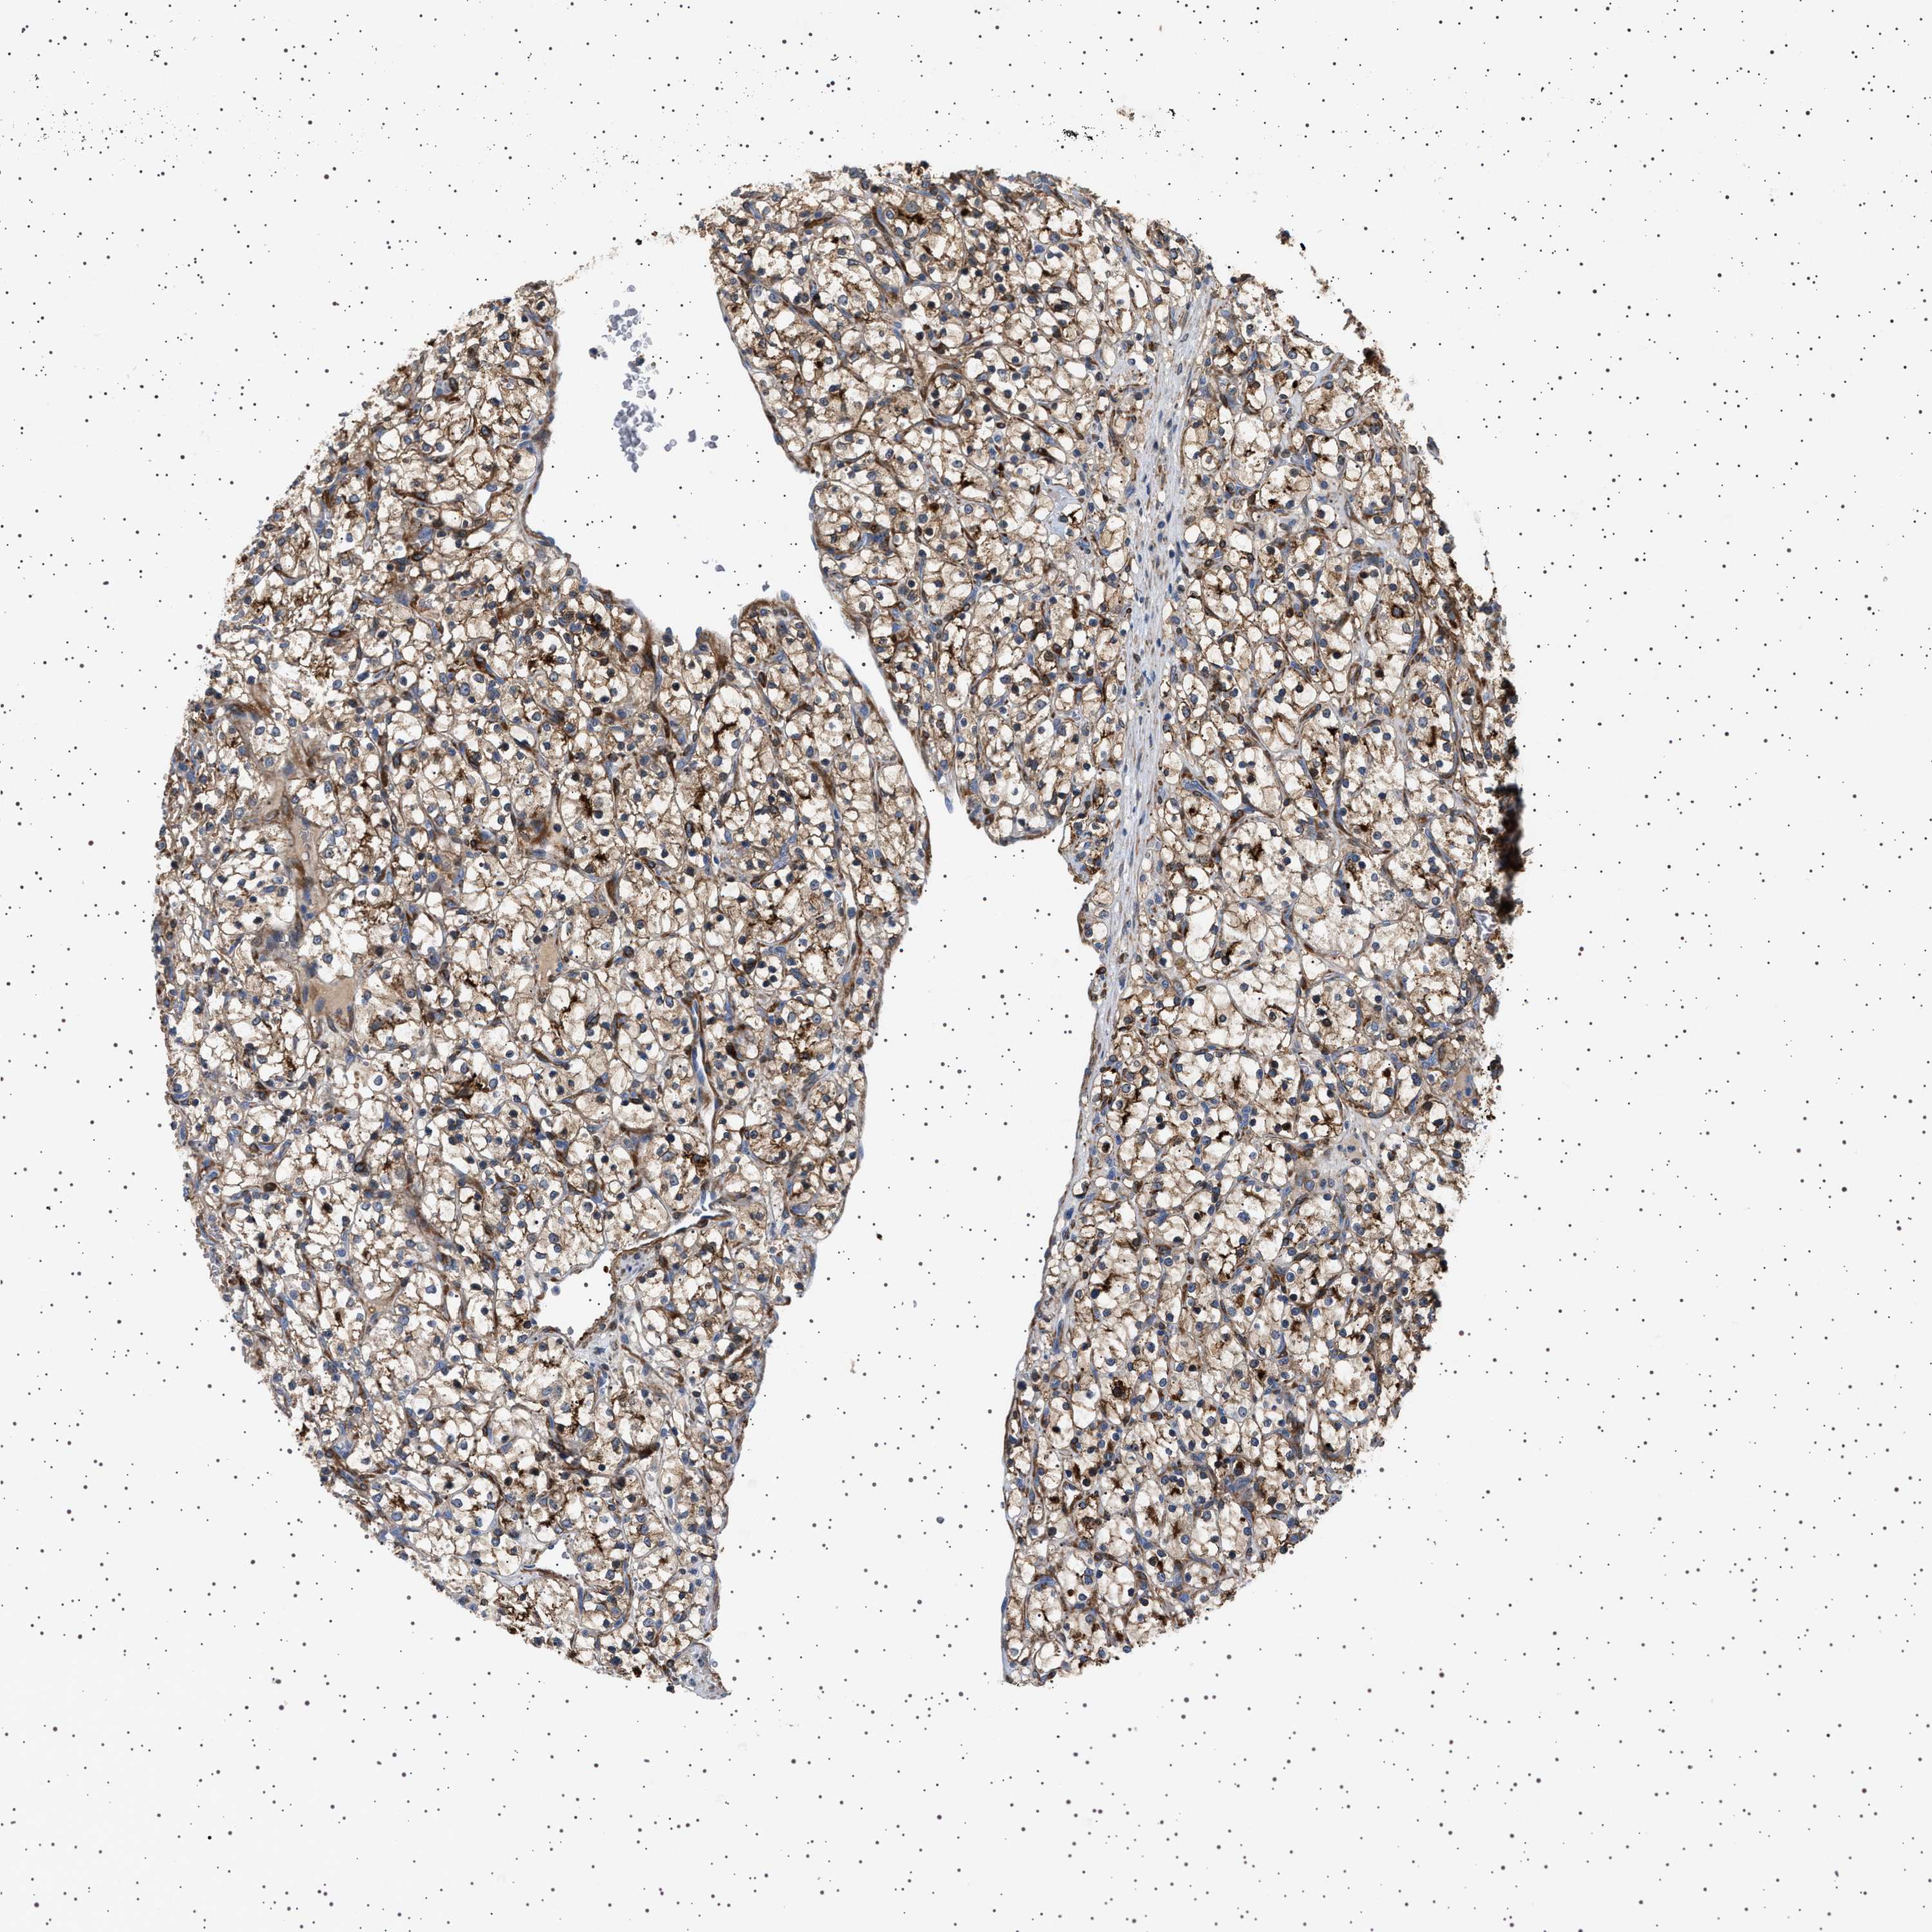

KIDNEY RENAL CLEAR CELL CARCINOMA (VALIDATION) - Interactive survival scatter ploti

The Survival Scatter plot shows the clinical status (i.e. dead or alive) for all individuals in the patient cohort, based on the same data that underlies the corresponding Kaplan-Meier plots. Patients that are alive at last time for follow-up are shown in blue and patients who have died during the study are shown in red.

The x-axis shows the expression levels (FPKM) of the investigated gene in the tumor tissue at the time of diagnosis. The y-axis shows the follow-up time after diagnosis (years). Both axes are complimented with kernel density curves demonstrating the data density over the axes. The top density plot shows the expression levels (FPKM) distribution among dead (red) and alive patients (blue). The right density plot shows the data density of the survived years of dead patients with high and low expression levels respectively, stratified using the cutoff indicated by the vertical dashed line through the Survival Scatter plot. This cutoff is automatically defined based on the FPKM cutoff that minimizes the p-score. The cutoff can be changed by dragging the vertical line or by entering a cutoff value in the square labeled "Current cut-off".

Under the Survival Scatter plot the p-score landscape (black curve; left axis) is shown together with dead median separation (red curve; right axis). Dead median separation is the difference in median mRNA expression between patients who have died with high and low expression, respectively. It is calculated as follows: median FPKM expression of dead patients with high expression - median FPKM expression of dead patients with low expression. This is intended to aid the user in visually exploring custom cutoffs and the associated p-scores and dead median separation.

Individual patient data is displayed and can be filtered by clicking on one or more of the category buttons on the top of the page. Categories describing expression level and patient information include: high, low, alive, dead, female, male and tumor stages. The scale of the x-axis can be toggled between linear and log-scale by clicking on the "x log" button. Mouse-over function shows TCGA ID, patient information and mRNA expression (FPKM) for each patient.

& Survival analysisi

Kaplan-Meier plots summarize results from analysis of correlation between mRNA expression level and patient survival. Patients were divided based on level of expression into one of the two groups "low" (under cut off) or "high" (over cut off). X-axis shows time for survival (years) and y-axis shows the probability of survival, where 1.0 corresponds to 100 percent.

GUCY1B1 is validated prognostic, high expression is favorable in Kidney Renal Clear Cell Carcinoma (validation)

Best expression cut offi

: 25.56

Median expressioni

TCGA RNA samplesi

Average pTPM 33.1

Number of samples 100